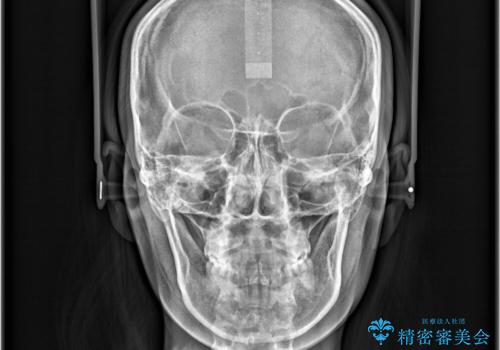

- 「歯のでこぼこと捻じれを治したい」を主訴に来院された患者様です。矯正検査の結果、上顎前歯がかなり唇側傾斜という結果になったので上下左右4番を抜歯をしワイヤー矯正で治療を行いました。

抜歯矯正でしたが順調に治療が進み2年で矯正治療を終えることが出来ました。歯のでこぼこや捻じれが治り、口元も下がって患者さんも大変満足されていました。